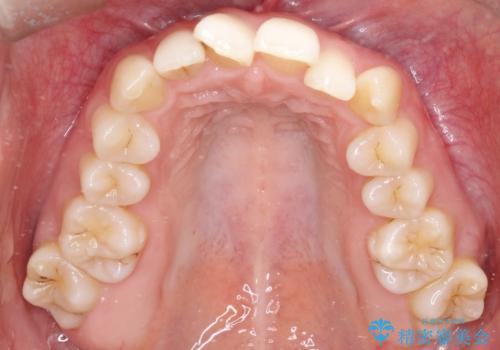

【インビザライン】 前歯の反対咬合を治したい

左下5番は先天性欠損のため乳歯は抜歯しインプラントにて欠損補綴しています。